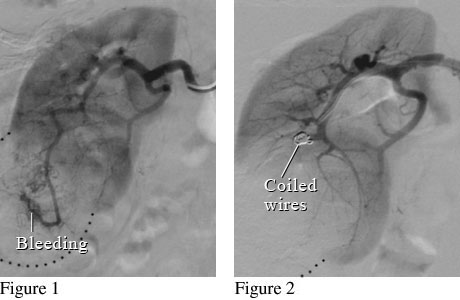

Figure 1 shows a kidney with a large mass that is bleeding. Figure 2 shows small coiled wires that have been placed in the artery to block the bleeding.